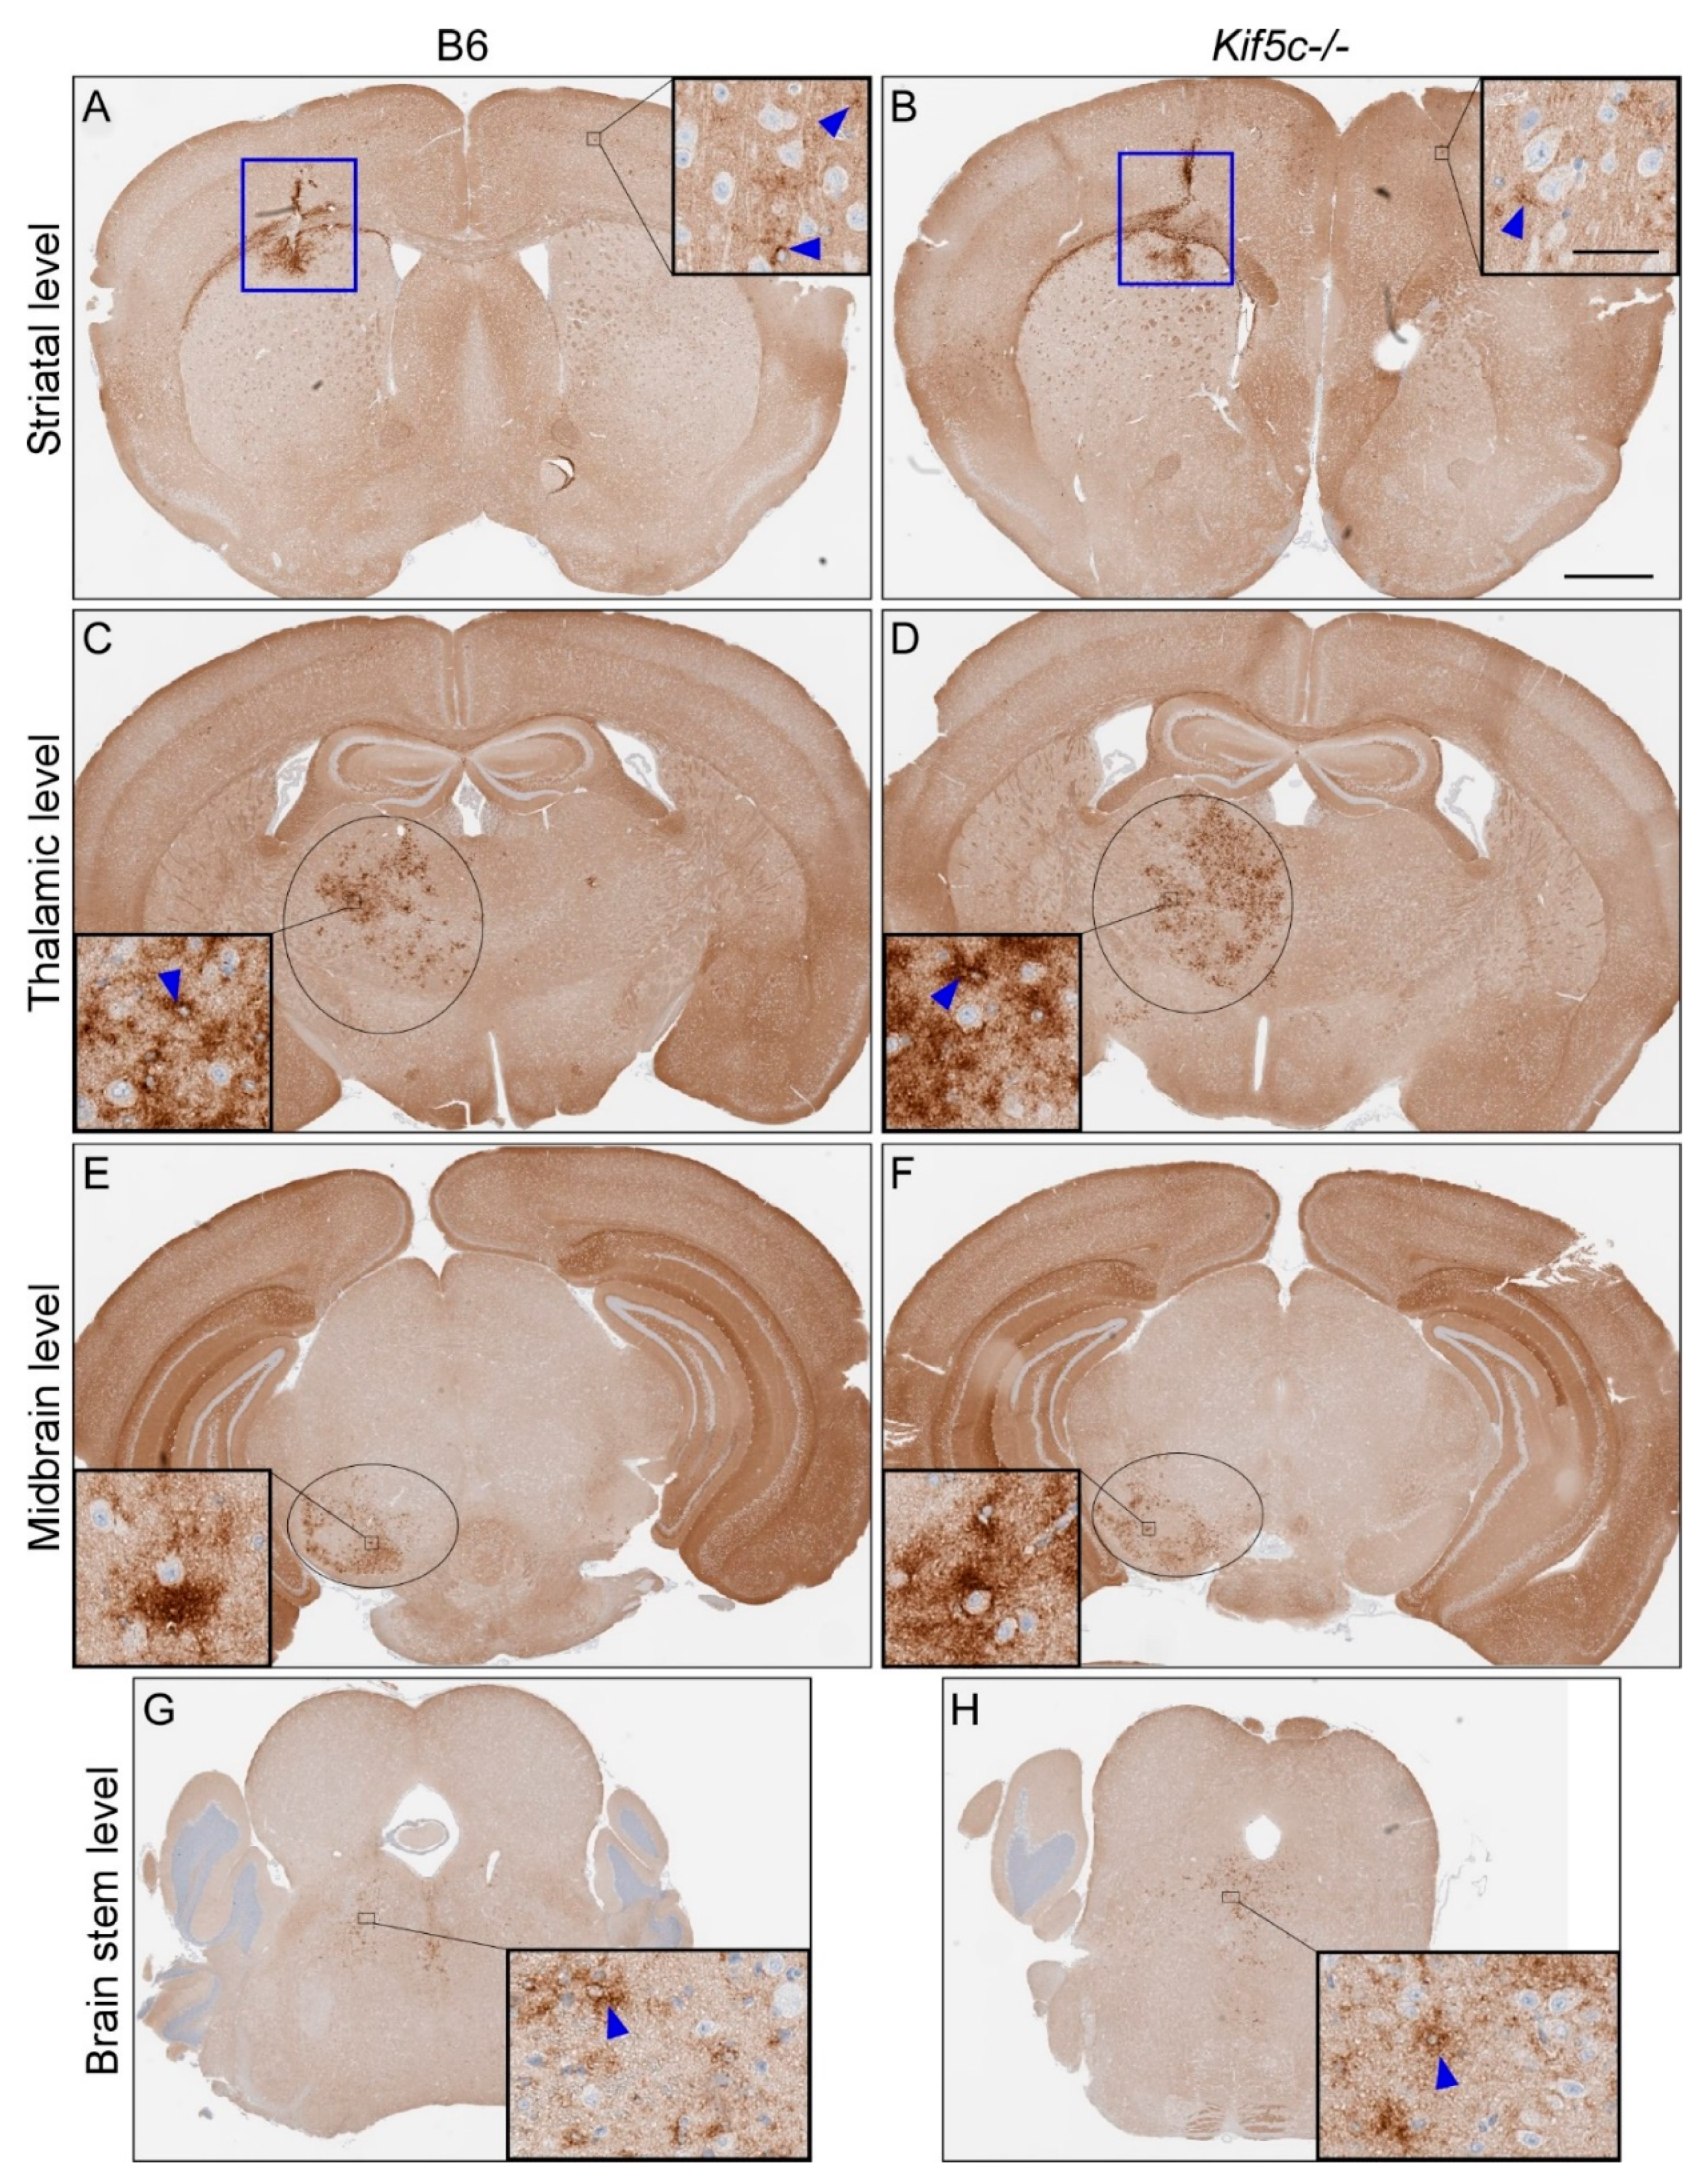

3.1. The 22 L PrPSc Spreading Kinetics in B6 and Kif5c−/− Mice

| Scrapie Strain | Mouse Strain | Time Point (dpi 2) | Brain Region | |||||||||

|---|---|---|---|---|---|---|---|---|---|---|---|---|

| Striatum (0) 1 | Thalamus (3.2) 1 | Midbrain (5) 1 | Rostral Pons (7) 1 | |||||||||

| PrPSc Present 3 | PrPSc Score 4 | PrPSc Present 3 | PrPSc Score 4 | PrPSc Present 3 | PrPSc Score 4 | p-Value 5 | PrPSc Present 3 | PrPSc Score 4 | p-Value 5 | |||

| 22 L | B6 | 7 | 2/2 | 1 | 0/2 | 0 | 0/2 | 0 | 0/2 | 0 | ||

| Kif5c−/− | 7 | 2/2 | 1 | 0/2 | 0 | 0/2 | 0 | 0/2 | 0 | |||

| B6 | 25 | 5/5 | 2 | 5/5 | 1 | 3/5 | 0–1 | 0.46 | 4/5 | 0–1 | >0.99 | |

| Kif5c−/− | 25 | 3/3 | 2 | 3/3 | 1 | 3/3 | 1 | 2/3 | 0–1 | |||

| B6 | 40 | 4/4 | 3 | 4/4 | 2 | 4/4 | 2 | 4/4 | 1 | >0.99 | ||

| Kif5c−/− | 40 | 4/4 | 3 | 4/4 | 2 | 4/4 | 2 | 3/4 | 1 | |||

| B6 | 60 | 3/3 | 2–3 | 3/3 | 3 | 3/3 | 1–2 | 3/3 | 1–2 | |||

| Kif5c−/− | 60 | 3/3 | 3 | 3/3 | 3 | 3/3 | 2 | 3/3 | 1–2 | |||